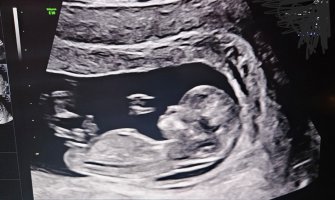

Tidlig jente, men det kan fremdeles skje ting.Dette ble tatt for et par uker siden, 11+6 ca ble det sagt/målt til. Kanskje litt tidlig men hva tror dere ?![]()

Men sikkert fordi jeg ikke helt skjønner hvor jeg skal seHvis du ser på den hvite lange streken som er helt til høyre på bilde ca midt midten på enden av magen liksom. Hvis det er en gutt så pleier den å stikke litt mer opp og av og til vil man se at det ligger flere små litt mer grå strekeroppå den hvite som man kaller stacking. Så må man se på vinkelen fra toppen på de strekene som man kaller for nub, og gjennom blæra parallelt med ryggraden. Nå hører jeg selv hvor avansert det høres ut, men om man ser på litt flere bilder av gutter og jenter så er det lettere å se forskjell. Jenter har ofte en hvit lang nub også er blæra høyt oppe mot nuben, mens på gutter er den litt lenger nede. Her så ser man en bitteliten sort prikk høyt oppe som er blæra. Så dette er en jenteÅåå,jeg synes ikke det var så lettMen sikkert fordi jeg ikke helt skjønner hvor jeg skal se

ahaaa!!! Gratulerer så mye med ei litta jente!! Så stas!Hvis du ser på den hvite lange streken som er helt til høyre på bilde ca midt midten på enden av magen liksom. Hvis det er en gutt så pleier den å stikke litt mer opp og av og til vil man se at det ligger flere små litt mer grå strekeroppå den hvite som man kaller stacking. Så må man se på vinkelen fra toppen på de strekene som man kaller for nub, og gjennom blæra parallelt med ryggraden. Nå hører jeg selv hvor avansert det høres ut, men om man ser på litt flere bilder av gutter og jenter så er det lettere å se forskjell. Jenter har ofte en hvit lang nub også er blæra høyt oppe mot nuben, mens på gutter er den litt lenger nede. Her så ser man en bitteliten sort prikk høyt oppe som er blæra. Så dette er en jente![]()

Ser jentete ut, men jeg klarer ikke se hvor blæra er. Hvor langt er du påvei?

13 +1 når ultralyden ble tattSer jentete ut, men jeg klarer ikke se hvor blæra er. Hvor langt er du påvei?

Da tenker jeg det burde vært stacking eller stått mer opp om det var en gutt. Så tenker jente13 +1 når ultralyden ble tatt![]()

Jeg vil si tidlig jente her, det er fremdeles tid for at den vil reise seg også ser jeg ikke helt hvor blæra er. Nuben har ikke tydelig stacking og er veldig parallell til ryggraden, men det er noe over nuben som kan være et ben eller noe som kan være stacking in progress, det vet jeg ikke, men det er fremdeles tidligVet ikke om det er bein eller nub på dette bilde, noen som kan si noe? De ville ikke si noe på sykehuset i dag. Fra en annen vinkel så man bare en liten tutt som hun sa kunne være både gutt og jente, men har ikke bilde av det. Målt til 12+2